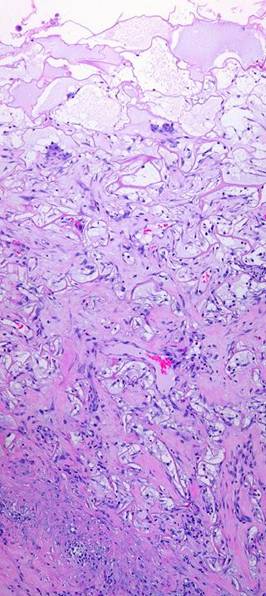

Figure 3

These five images demonstrate the absence and suppression of inflammation.  Figures 3a, b, c were taken from a patient having lower extremity dermatofasciectomy for primary lymphedema (Milroy’s, praecox).

(3a, top left)  Biopsy was taken 4 hours after the fasciectomy, just prior to Integra.  Normal post-traumatic thrombosis has recognized the injury, attracting polymorphonuclear leukocytes (neutrophils) which are densely marginated in blood vessels on the wound surface.  This is the normal response to injury, the start of inflammation.

(3b, top right)  Biopsy was taken 4 hours later after placing Integra.  A blood vessel is present at the wound surface between Integra matrix (top and left) and normal adipose (bottom and right).  Leukocyte margination and migration are present, but not dense

(3c, middle, left)  At 24 hours the only neutrophils are a few, in proportion to the red cells that bled into the matrix.  Figures 3d, e are from a similar patient.

(3d, middle, right)  At 5 days, the only cells present are early histogenetic pioneer and transitional cells.  There are no neutrophils, no plasma cells, no eosinophils, no lymphocytes, no monocyte-macrophages.  Other than some late foreign body giant cells occurring along the silicone, at no time does a defensive response ever appear in the matrix.

(3e, bottom)  At 11 days, the matrix remains mostly devoid of cells in this locale, although the entrainment of cells starting to migrate toward the matrix is apparent at lower right.  (Note 1:  Cell migration and histogenesis occur casually at different rates throughout the matrix, and it is common that a somewhat later image (3e at 11 days) might appear less populated than an earlier image from a different area (3d at 5 days);  this variability of time with Integra is the norm.  Note 2:  Unless otherwise stated or obvious, all histological images presented throughout the chapter are oriented with the outer superficial surface, silicone or epidermis, at the top.)